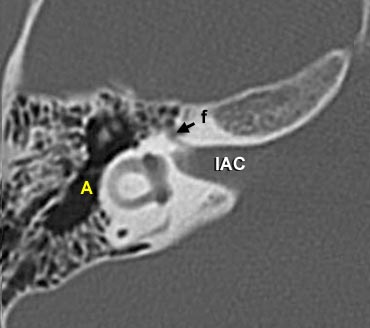

- IAC = Ống tai trong (internal auditory canal)

Đoạn mê đạo của dây thần kinh mặt xuất phát từ ống tai trong, chạy gần như vuông góc với trục dài của xương đá về phía trước để đến hạch gối (geniculate ganglion).

Tại hạch, dây thần kinh mặt tạo thành một vòng chữ U (gối thứ nhất của dây thần kinh mặt) để chạy ra phía sau như đoạn nhĩ dọc theo thành trong của thượng nhĩ.

Một lát cắt coronal hơi ra phía sau hơn sẽ cho thấy dây thần kinh mặt hai lần.

Phần phía trong là đoạn thoát ra khỏi ống tai trong và chạy về phía hạch gối (mũi tên trắng phía trong).

Phần phía ngoài là đoạn chạy theo hướng ra sau, xuất phát từ vòng chữ U của gối thứ nhất.